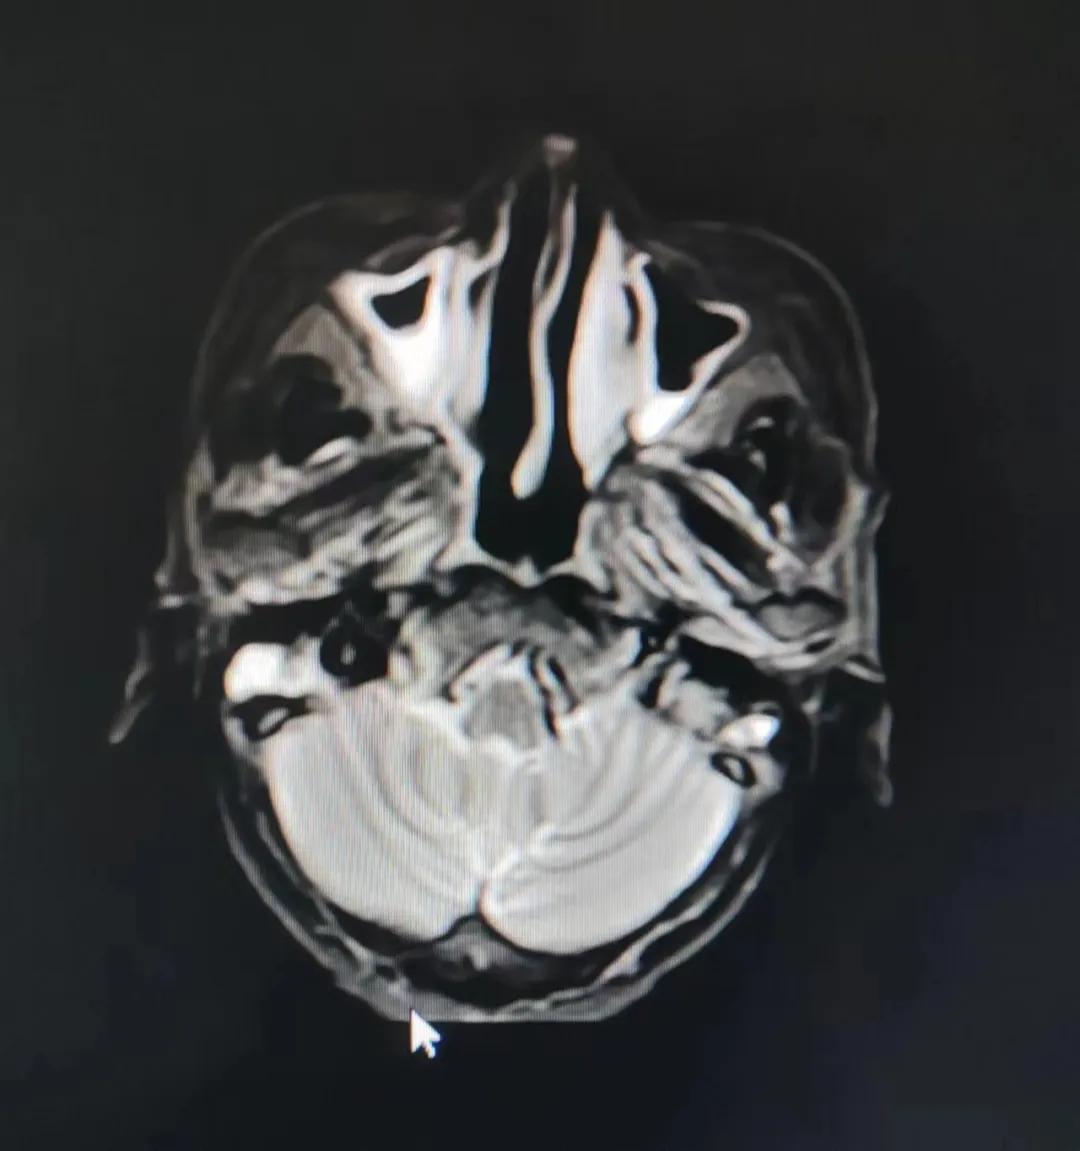

治療前

考慮到患者年齡較大、體質(zhì)差,手術(shù)難度大,且常規(guī)的放射治療難以保護(hù)患者晶體造成患者雙眼視力損傷,放療團(tuán)隊(duì)以最快的速度制定了精準(zhǔn)放射治療方案并開(kāi)始為其實(shí)施治療。僅僅數(shù)日后,老人腫塊出血即得到控制,腫塊明顯縮小,放療20次后腫塊迅速縮??!